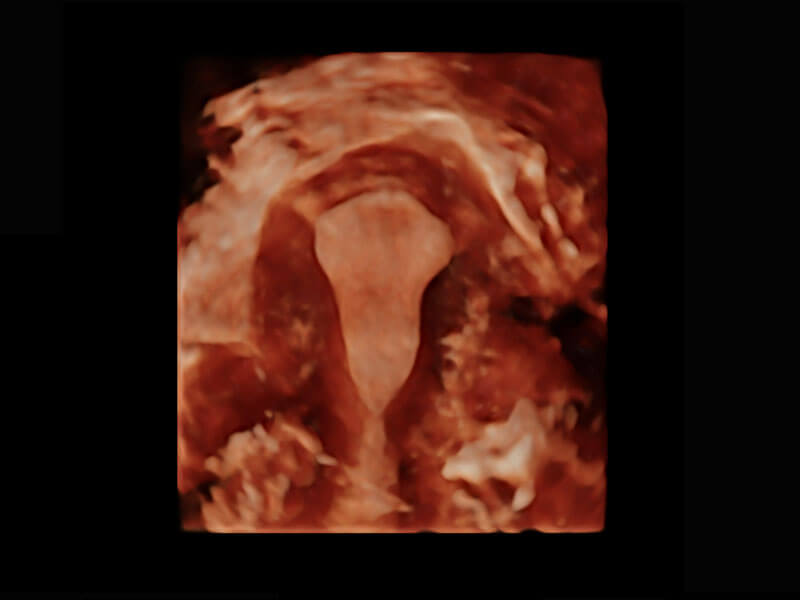

腔内三维-宫内节育器

腔内三维-光影成像

P60优异的图像质量搭载专科探头,在妇科基础疾病的诊断、卵泡生长的监测、输卵管通畅情况的判别等方面为您提供生殖应用方案。